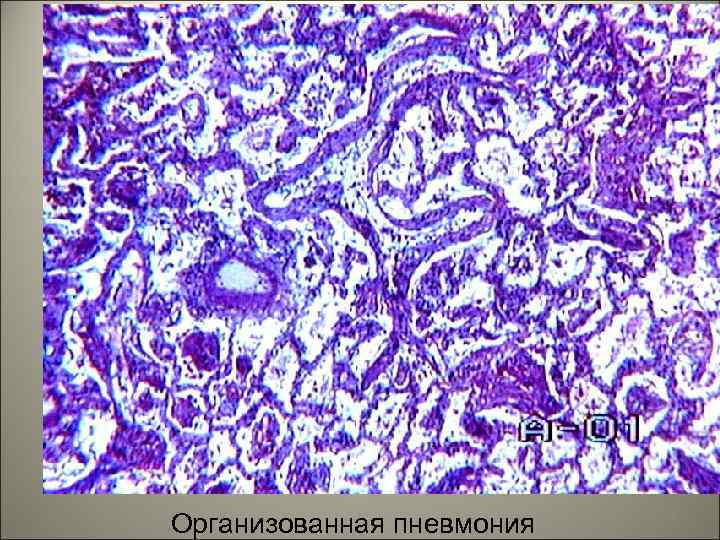

• Осложнения. Легочные: карнификация, абсцесс, гангрена, эмпиема плевры. 55

• Карнификация развивается в связи с нарушением фибринолитической функции нейтрофилов, массы фибрина не расплавляются и подвергаются организации, т. е. прорастают грануляционной тканью, которая образует зрелую волокнистую соединительную ткань. Легкое превращается в безвоздушную плотную ткань. 56

Организованная пневмония 79